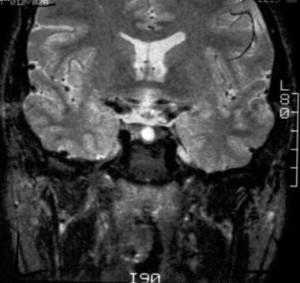

Киста кармана Ратке представляет собой редко встречающееся образование из остатков эмбриональной эктодермы (щель Ратке), расположенное между долями гипофиза. Выявляется в любом возрасте, но чаще в 50-60 лет. Клинические проявления связаны с масс-эффектом. При головного мозга выявляется небольшая (3-5 мм) киста с четким контуром, без отека вокруг, однородная по структуре. Сигнал зависит от содержимого. При серозном содержимом сигнал типично жидкостный, при мукоидном киста светлая на Т1-взвешенных МРТ. В редких случаях киста достигает больших размеров и даже выходит за пределы седла. Стенка кисты иногда усиливается при контрастировании.

МРТ головного мозга. Т2-взвешенная корональная МРТ. Киста кармана Ратке.

Общепринятым и стандартным способом диагностики ККР является метод МРТ. Данный способ позволяет определить место локализации кисты, ее размеры и контакты с функционально значимыми зонами мозга, а также основными магистральными сосудами. В зависимости от состава содержимого ККР представлены гипо-, изо- или гиперинтенсивными на Т1- и Т2-ВИ. Кальцификация стенок кисты встречается крайне редко. При болюсном введении парамагнетика эти образования не накапливают контрастное вещество. ККР с мукозным содержимым представляются гиперинтенсивными как на Т2-ВИ, так и на Т1-ВИ; серозное содержимое ККР соответствует сигналу ликвора, т. е. гипоинтенсивный сигнал на Т1-ВИ и гиперинтенсивный сигнал на Т2-ВИ. Однако ККР с высоким содержанием белка являются гиперинтенсивными на Т1-ВИ и гипоинтенсивными на Т2-ВИ. На основе многочисленных МР-исследований и гистологических верификаций кистозных образований гипофиза можно предположить, что наличие внутрикистозного муцинозного включения патогномонично для ККР в 70 - 80% случаев. При контрастном усилении в большинстве случает накопление отсутствует, однако может быть виден тонкий контрастирующий ободок окружающей сжатой гипофизарной ткани. Примерно в 75% случаев можно выявить небольшой неконтрастирующий внутрикистозный узелок, который фактически является патогномоничным признаком кисты расщелины Ратке. Иногда можно увидеть уровень жидкости-жидкости (особенно если было кровоизлияние).

Киста кармана Ратке представляет собой редко встречающееся образование из остатков эмбриональной эктодермы (щель Ратке), расположенное между долями гипофиза. Выявляется в любом возрасте, но чаще в 50-60 лет. Клинические проявления связаны с масс-эффектом. При МРТ головного мозга выявляется небольшая (3-5мм) киста с четким контуром, без отека вокруг, однородная по структуре. Сигнал на МРТ головного мозга зависит от содержимого. При серозном содержимом сигнал типично жидкостный, при мукоидном киста светлая на Т1-взвешенных МРТ головного мозга. В 70-80% случаев внутри кисты выявляется неконирастирующийся узелок («пятно») - признак патогномоничный для кисты кармана Ратке. В редких случаях киста достигает больших размеров и даже выходит за пределы седла. Стенка кисты иногда усиливается при МРТ головного мозга с контрастированием. Дифференциальная диагностика при МРТ головного мозга должна проводиться с арахноидадьной и эпидермоидной кистами, тератомой, кистозной аденомой гипофиза и краниофарингиомой. Иногда при МРТ головного мозга киста кармана Ратке напоминает “пустое” турецкое седло. При маленьких размерах кисты ее на до дифференцировать на МРТ с микроаденомой гипофиза.